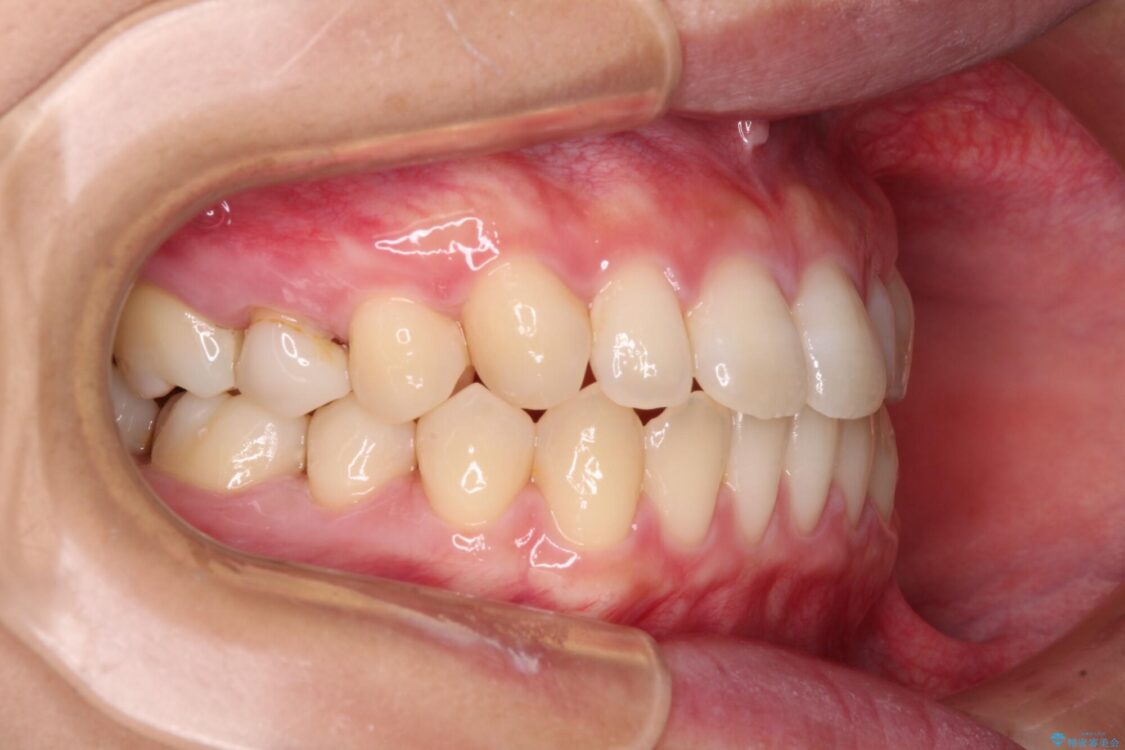

治療後

• 隙間だらけの歯列 インビザラインで改善 治療後画像

治療後について

空隙歯列(すきっ歯)は、舌の突出癖をある程度改善できたとしても、後戻りにより隙間が開きやすいと言われています。

裏側から細いワイヤーで保定するとともに、睡眠時のマウスピース装着を徹底していただくことで、後戻りを最小限にとどめます。